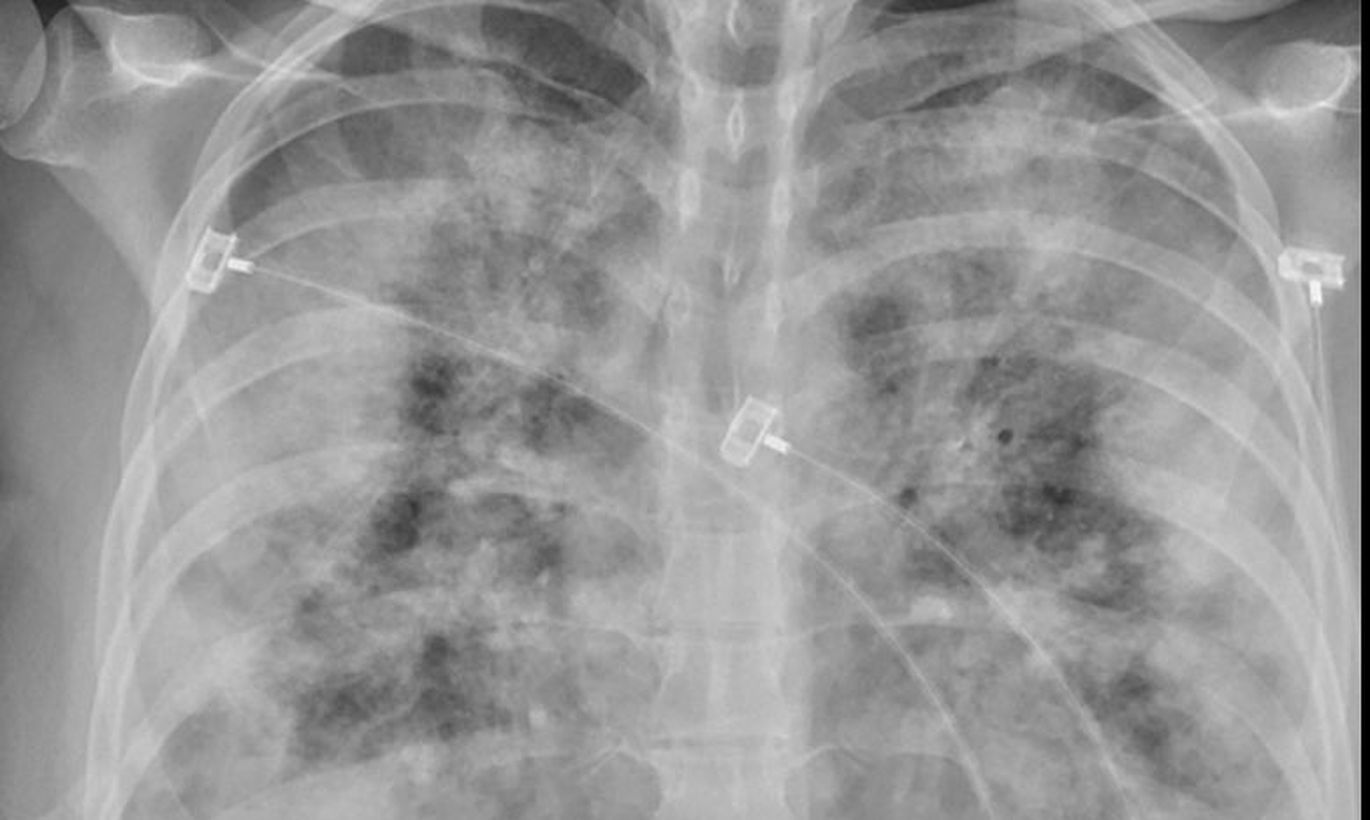

Вакцинация от Covid-19 полностью не защищает от заражения коронавирусом, однако различия заметны, если наблюдать за самим ходом болезни. Сравнение двух рентгеновских снимков ясно показывает, как это выражается по отношению к повреждениям легких.

Однако факт, что вакцины защищают, по-прежнему в силе. Поэтому те, кто вакцинирован и все-таки заразился коронавирусом, может считаться с куда более легким течением болезни, чем невакцинированные лица. То, насколько велико различие, наглядно видно на сравнении двух рентгеновских снимков.

На рентгеновских снимках, которыми в Twitter поделился руководитель отдела инфекционных заболеваний Университета Мэриленда Фахим Йоунус, можно увидеть очень разные легкие. В обоих случаях это легкие пациентов, зараженных Covid-19, однако на одном снимке видно гораздо больше светлых теней, чем на втором. Белые тени - так называемое "матовое стекло", возникающее при воспалении легких. Если в тканях накапливается вода, то на рентгеновских снимках она видна как "светлые облака". На втором снимке легких такого эффекта практически нет. Это легкие вакцинированного от Covid-19 человека, который очевидно лучше перенес инфекцию.